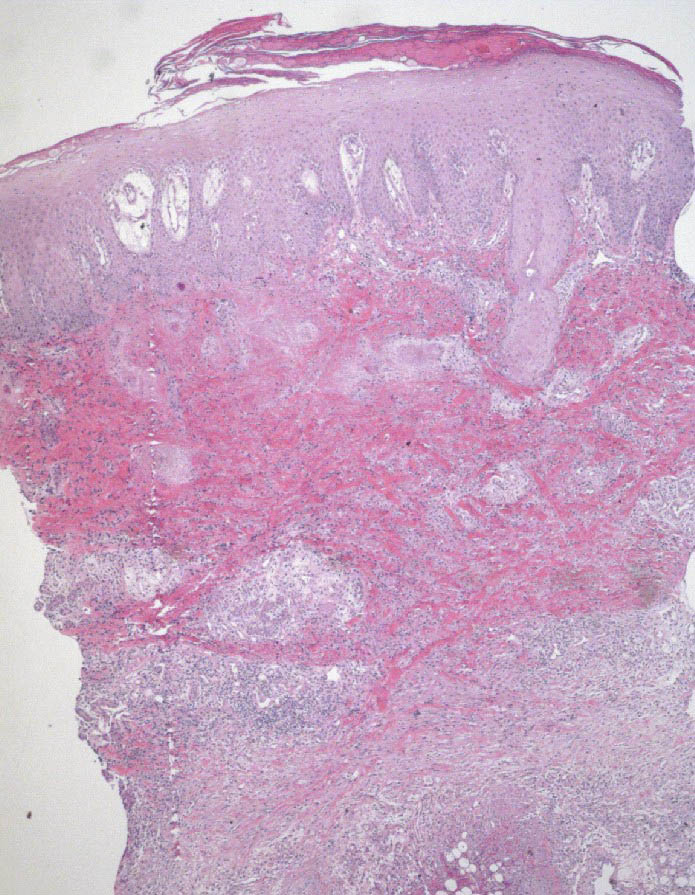

Aspergillosis= داء الفطور الرشاشية